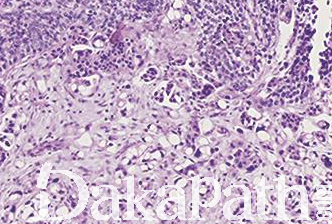

浸润性尿路上皮癌,富脂质

Infiltrating urothelial carcinoma, Lipid-rich

尿路上皮癌瘤细胞胞浆内存在多个空泡挤压核形成类似于脂肪母细胞的瘤细胞

特征性形态学改变是存在大的脂肪母细胞样细胞,具有 1 个或多个胞浆空泡,挤压细胞核;

常和其它类型或普通型尿路上皮癌混合存在,脂质细胞通常占肿瘤成分的 10%-50%,